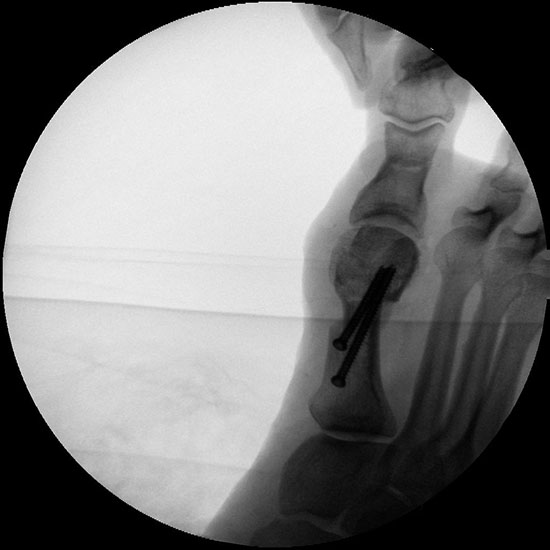

Abbildung 1

• Korrekturpotential größer als beim offenen Chevron, da die Gelenkkapsel als stabilisierendes Element erhalten bleibt und über eine trikortikale Osteosynthese mit zwei kanülierten Schrauben eine Verschiebung bis ca. 80% des Metatarsaledurchmessers möglich ist (Abb. 1).